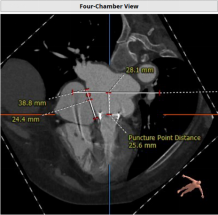

CT评估:既往植入佰仁生物瓣,25#,True ID 23mm, 高度17mm,房间隔穿刺高度约为25.6mm, 模拟植入23mm SAPIEN 3后,Neo-LVOT 153.7mm2 小于170 mm2,aorta-mitral 平面角度125.9°,mitral-septum distance 3mm,有流出道狭窄风险。CT推荐角度为RAO 40°,房间隔无明显钙化、膨出,房间隔长度可满足穿刺需要。拟植入SAPIEN 3 23mmPLUS3ml。